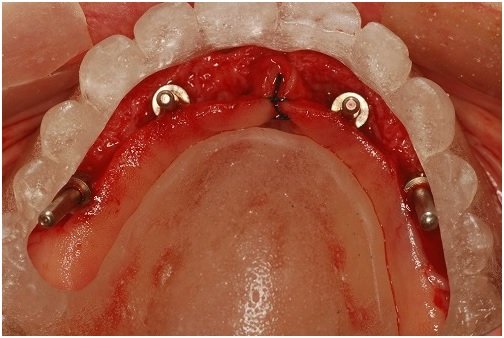

Mesmo não gostando, em muitas situações somos quase obrigados a utilizar este dispositivo, como em casos de desdentados totais em que perdemos todas as referências (Figura 2). Desta forma, um guia deve ser confeccionado com base nas características anatômicas de cada região, e o seu desenho deve estar diretamente relacionado com a disponibilidade óssea oferecida e a disposição dos futuros dentes. De nada adianta a projeção de um guia com dentes muito bem posicionados em áreas que não ofereçam estrutura óssea suficiente para se colocar implantes que viabilizem estes dentes. Portanto, o guia cirúrgico só poderá ser finalizado após a realização de todos os exames pré-operatórios, o que inclui enceramento de diagnóstico e radiografias, de preferência tomografias que nos deem imagens mais fiéis e com desenho da espessura óssea.

Figura 2 – Guia cirúrgico posicionado checando o posicionamento dos implantes por meio dos indicadores de paralelismo. Observar a dificuldade de visualização do campo devido à parte acrílica palatal.